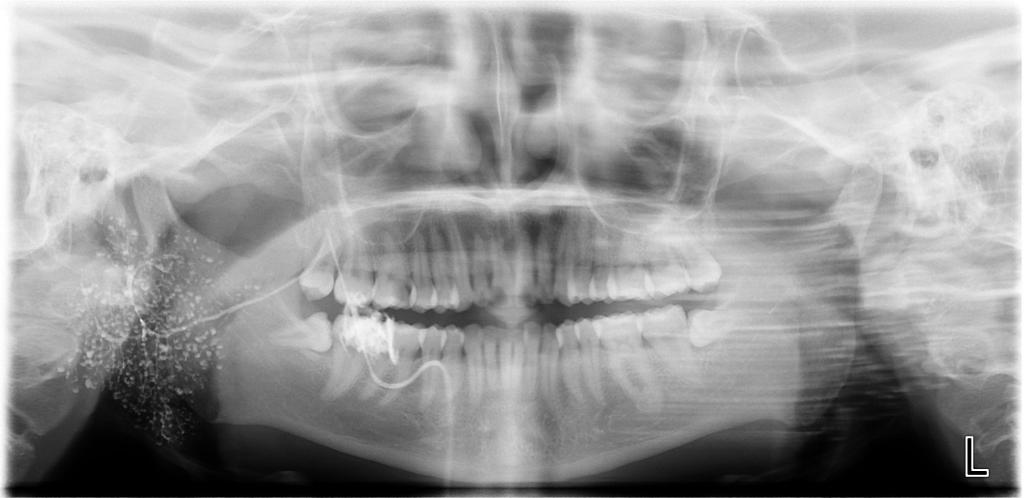

数字化口腔曲面体层片

常规开展:数字化根尖片/横断牙合片、数字化口腔曲面体层片、头影测量侧位/正位片、手腕骨片、颅颌面CBCT、牙齿CBCT的检查以及涎腺造影、窦道 瘘管造影。

诊断范围涉及牙体牙髓病、牙周病、阻生牙/多生牙定位、种植牙术前CT评估分析、颞下颌关节CT诊断分析、,颌骨及涎腺疾病、颌面发育畸形、正畸治疗辅助诊断等大部分颌面部疾病,为临床医疗提供强有力的支持。